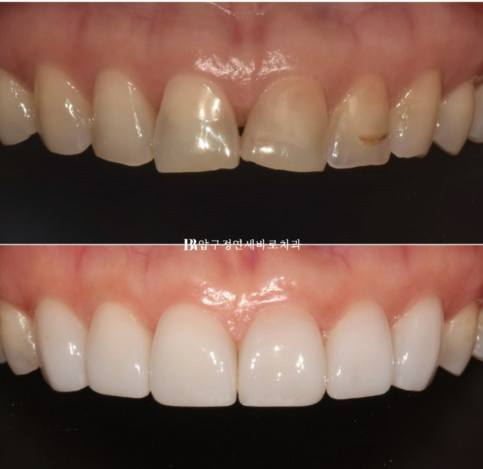

This patient came in to receive no-prep laminate veneers for the front teeth in their 50s.

They wanted to fix the uneven discoloration of the front teeth caused by resin cavity treatments they had received over the years.

This is the result after the final laminate veneer treatment was completed.

The subtle, natural translucency is one of the strengths of Yonsei Baro Dental Clinic’s no-prep laminate veneer, Gelami.

No-prep Gelami laminate veneers were placed on the six front teeth from canine to canine.

The worn and chipped edges of the teeth have been beautifully covered.

The uneven resin stains have also been concealed.

The last photo is after Gelami placement.

Even after placement, they are made so thin that there is little difference from the original teeth.